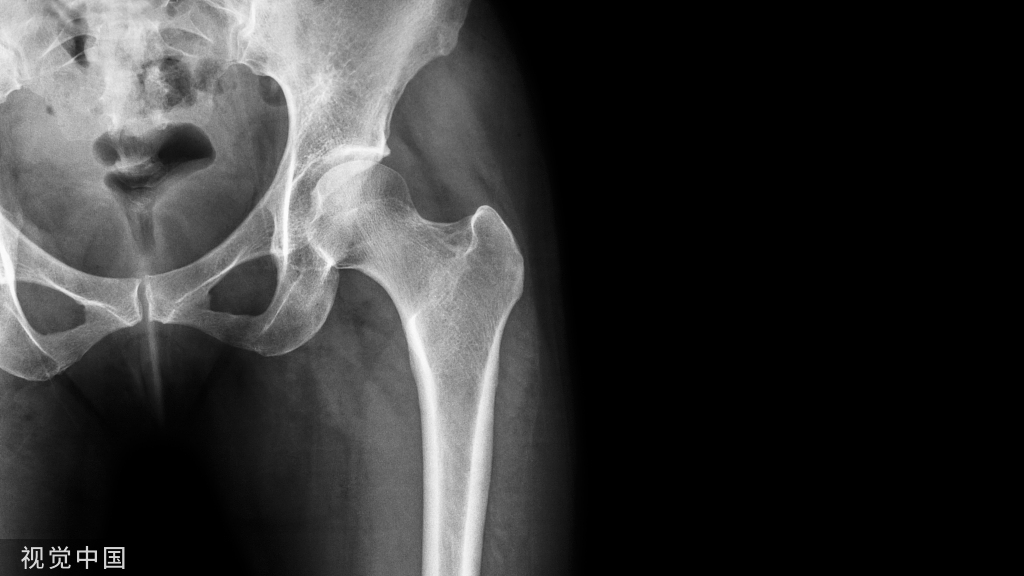

半月板在膝关节应力传递中起着重要的作用,半月板通过增加关节面接触面积来分配机械应力,下肢对线异常(内翻或外翻)可改变膝关节的应力分布而导致膝关节间室(内侧或外侧)超负荷,既往文献表明膝关节对齐不良(力线异常)可能是半月板后根撕裂的危险因素。内侧半月板后根部撕裂是指内侧半月板后角与胫骨连接部位发生的撕脱以及1cm以内的放射状撕裂,当半月板根部发生断裂或撕脱损伤时,将会导致半月板对抗环形压力的功能丧失,出现半月板的外凸,失去保护关节软骨的功能,继而膝关节会发生退行性改变。内侧半月板后根部撕裂的发病率约占所有半月板撕裂的10.1%-27.8%,主要见于50-65岁偏肥胖的女性膝内翻骨关节炎患者。内侧半月板后根撕裂会出现半月板外凸,失去半月板功能。如何做到半月板中央化和恢复半月板的功能是治疗内侧半月板后根撕裂的前提与基础,是近几年的热门话题。很多文献报道,不考虑力线的影响因素,单纯缝合半月板治疗效果不满意。因此治疗半月板撕裂尤其是出现半月板外凸的情况下,应评估下肢力线的情况。天津医院陈德生、黄竞敏,山东中医药大学附属医院杨久山,广东省中医院杨伟毅,安徽省立医院赵其纯等都在会议学术交流中展示HTO手术治疗膝内侧半月板后根撕裂病例并取得良好疗效。下面介绍关节周围截骨治疗半月板损伤的最新相关文献。

Jung等人分析了26例内侧开放楔形胫骨高位截骨术(MOWHTO)患者,在术前和术后3个月、6个月、1.5年和2年使用MRI测量内侧半月板挤压情况。发现术后6个月内侧半月板挤压情况显著改善,随着时间的推移,情况进一步改善,术前胫骨近端内侧角(MPTA)和术后内侧半月板挤压情况显著相关[1]